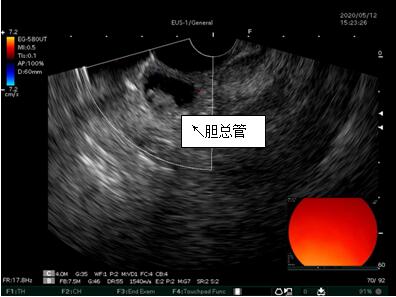

69歲王姓患者,因“發(fā)現(xiàn)無痛性黃疸1月”入院,根據(jù)患者病史,患者診斷傾向于壺腹部腫瘤所致梗阻性黃疸。予以完善腹部CT及上腹部MRI加MRCP均顯示肝內(nèi)外膽管擴(kuò)張,未發(fā)現(xiàn)明顯膽管,胰腺及十二指腸乳頭部腫瘤,且患者CA199正常。以前醫(yī)院未引進(jìn)超聲內(nèi)鏡,這類患者到此就遇到診斷瓶頸。此患者經(jīng)過消化內(nèi)科張丹霞副主任醫(yī)師完善超聲內(nèi)鏡檢查后,可以清楚顯示膽總管下段壁內(nèi)軟組織占位?;颊咄ㄟ^超聲內(nèi)鏡檢查診斷明確,轉(zhuǎn)至肝膽外科行手術(shù)治療。

超聲胃鏡圖片

膽總管小腫瘤性病變CT及MRI檢查陽性率偏低,因其低代謝特征,PET-CT陽性率也偏低,超聲內(nèi)鏡對(duì)這類疾病的診斷陽性率是所有檢查中最高的,且可行穿刺活檢進(jìn)一步確診病灶性質(zhì)。

環(huán)掃超聲內(nèi)鏡主要用于胃腸道粘膜下腫物診斷,胃腸道腫瘤分期,發(fā)現(xiàn)早期胃癌等,扇掃超聲內(nèi)鏡主要用于診斷膽道及胰腺疾病,并且可行穿刺活檢取病理。